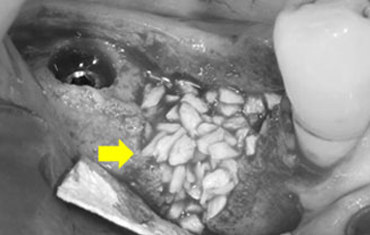

매복된 제2 대구치

매복된 사랑니

견고한 금속 차폐막 적용